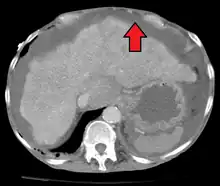

Ascites in a person with abdominal cancer as seen on ultrasound

Liver cirrhosis with ascites

Ultrasound investigation is often done before attempts to remove fluid from the abdomen. This may reveal the size and shape of the abdominal organs, and Doppler studies may show the direction of flow in the portal vein, as well as detecting Budd–Chiari syndrome (thrombosis of the hepatic vein) and portal vein thrombosis. The sonographer also can estimate the amount of ascitic fluid, and difficult-to-drain ascites may be drained under ultrasound guidance. An abdominal CT scan is more accurate than a sonogram to reveal abdominal organ structure and morphology.[12]